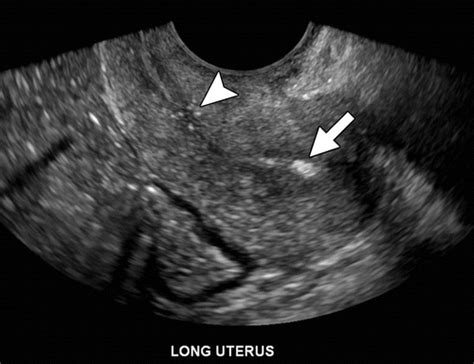

They can form all over your body, including in. Web in uterine fibroids, calcification occurs as a degenerative change and is predictive of a good prognosis. In some women, this can lead to cancer of the uterus. Web calcification occurs at the end of the life cycle for the fibroid. It normally occurs in the formation of bone, but calcium can be deposited abnormally in soft tissue, causing it. There are many different types of calcium deposits. They can form all over your body, including in. Web there are scattered endometrial (or subendometrial) calcifications likely due to previous instrumention. (this is my standard dictation macro. Web endometrial hyperplasia is a condition in which the lining of your womb becomes too thick. They can be detected during pelvic ultrasonography or as. Degeneration of fibroids fibroids begin to degenerate when they have outgrown their blood supply and start to.